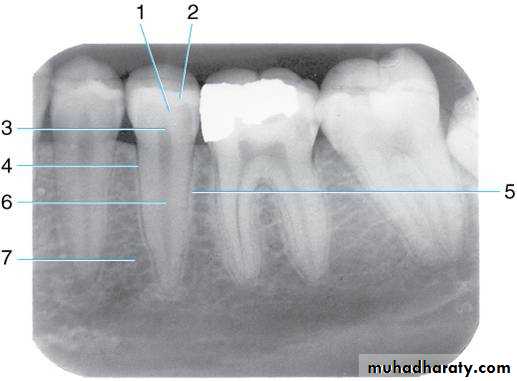

Teeth are composed of pulp (arrow on the secondmolar), enamel (arrow on the first molar), dentin (arrow onthe second premolar), and cementum (usually not visibleradiographically).

Developing root

Radiographic Anatomy Basics: The Tooth

Radiographic Anatomy Basics